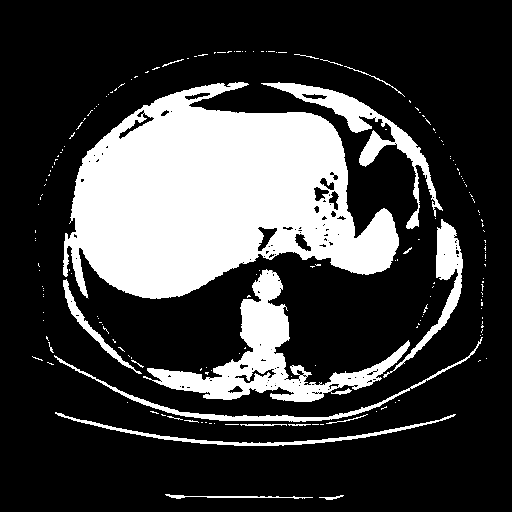

Reconstructed NATIVE CT scan (cycle consistency)

Full window (WL 1023.5, WW 4095 β†’ Low βˆ’1024, High +3071)

Actual HU range: [-1024.0, 3071.0]